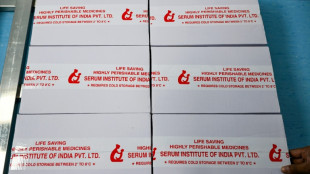

Una vacuna contra la malaria de una empresa india se distribuirá en África en mayo